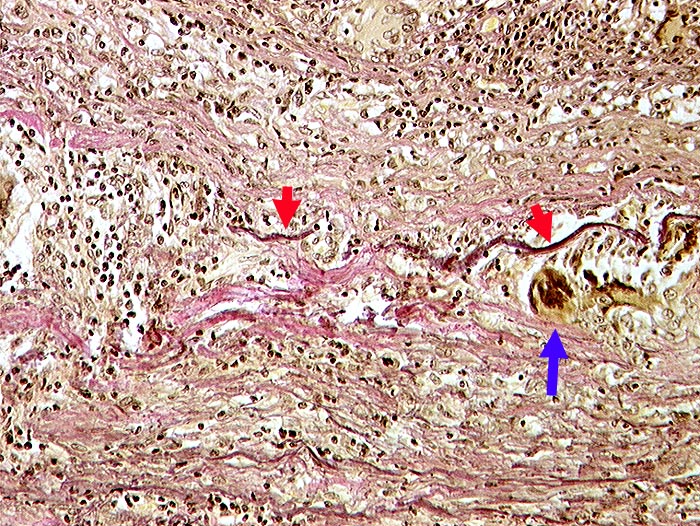

PathoPic ID 237 - Riesenzellarteriitis der Arteria carotis interna

Riesenzellarteriitis der Arteria carotis interna

Dichtes lymphohistiozytäres Entzündungsinfiltrat in der Gefässwand.

Riesenzellen phagozytieren die bereits fragmentierte

Lamina elastica externa.

Primäre Vaskulitis mit Befall grosser Gefässe, bevorzugt extrakranielle Äste der Arteria carotis. Temporalarterie häufig betroffen.